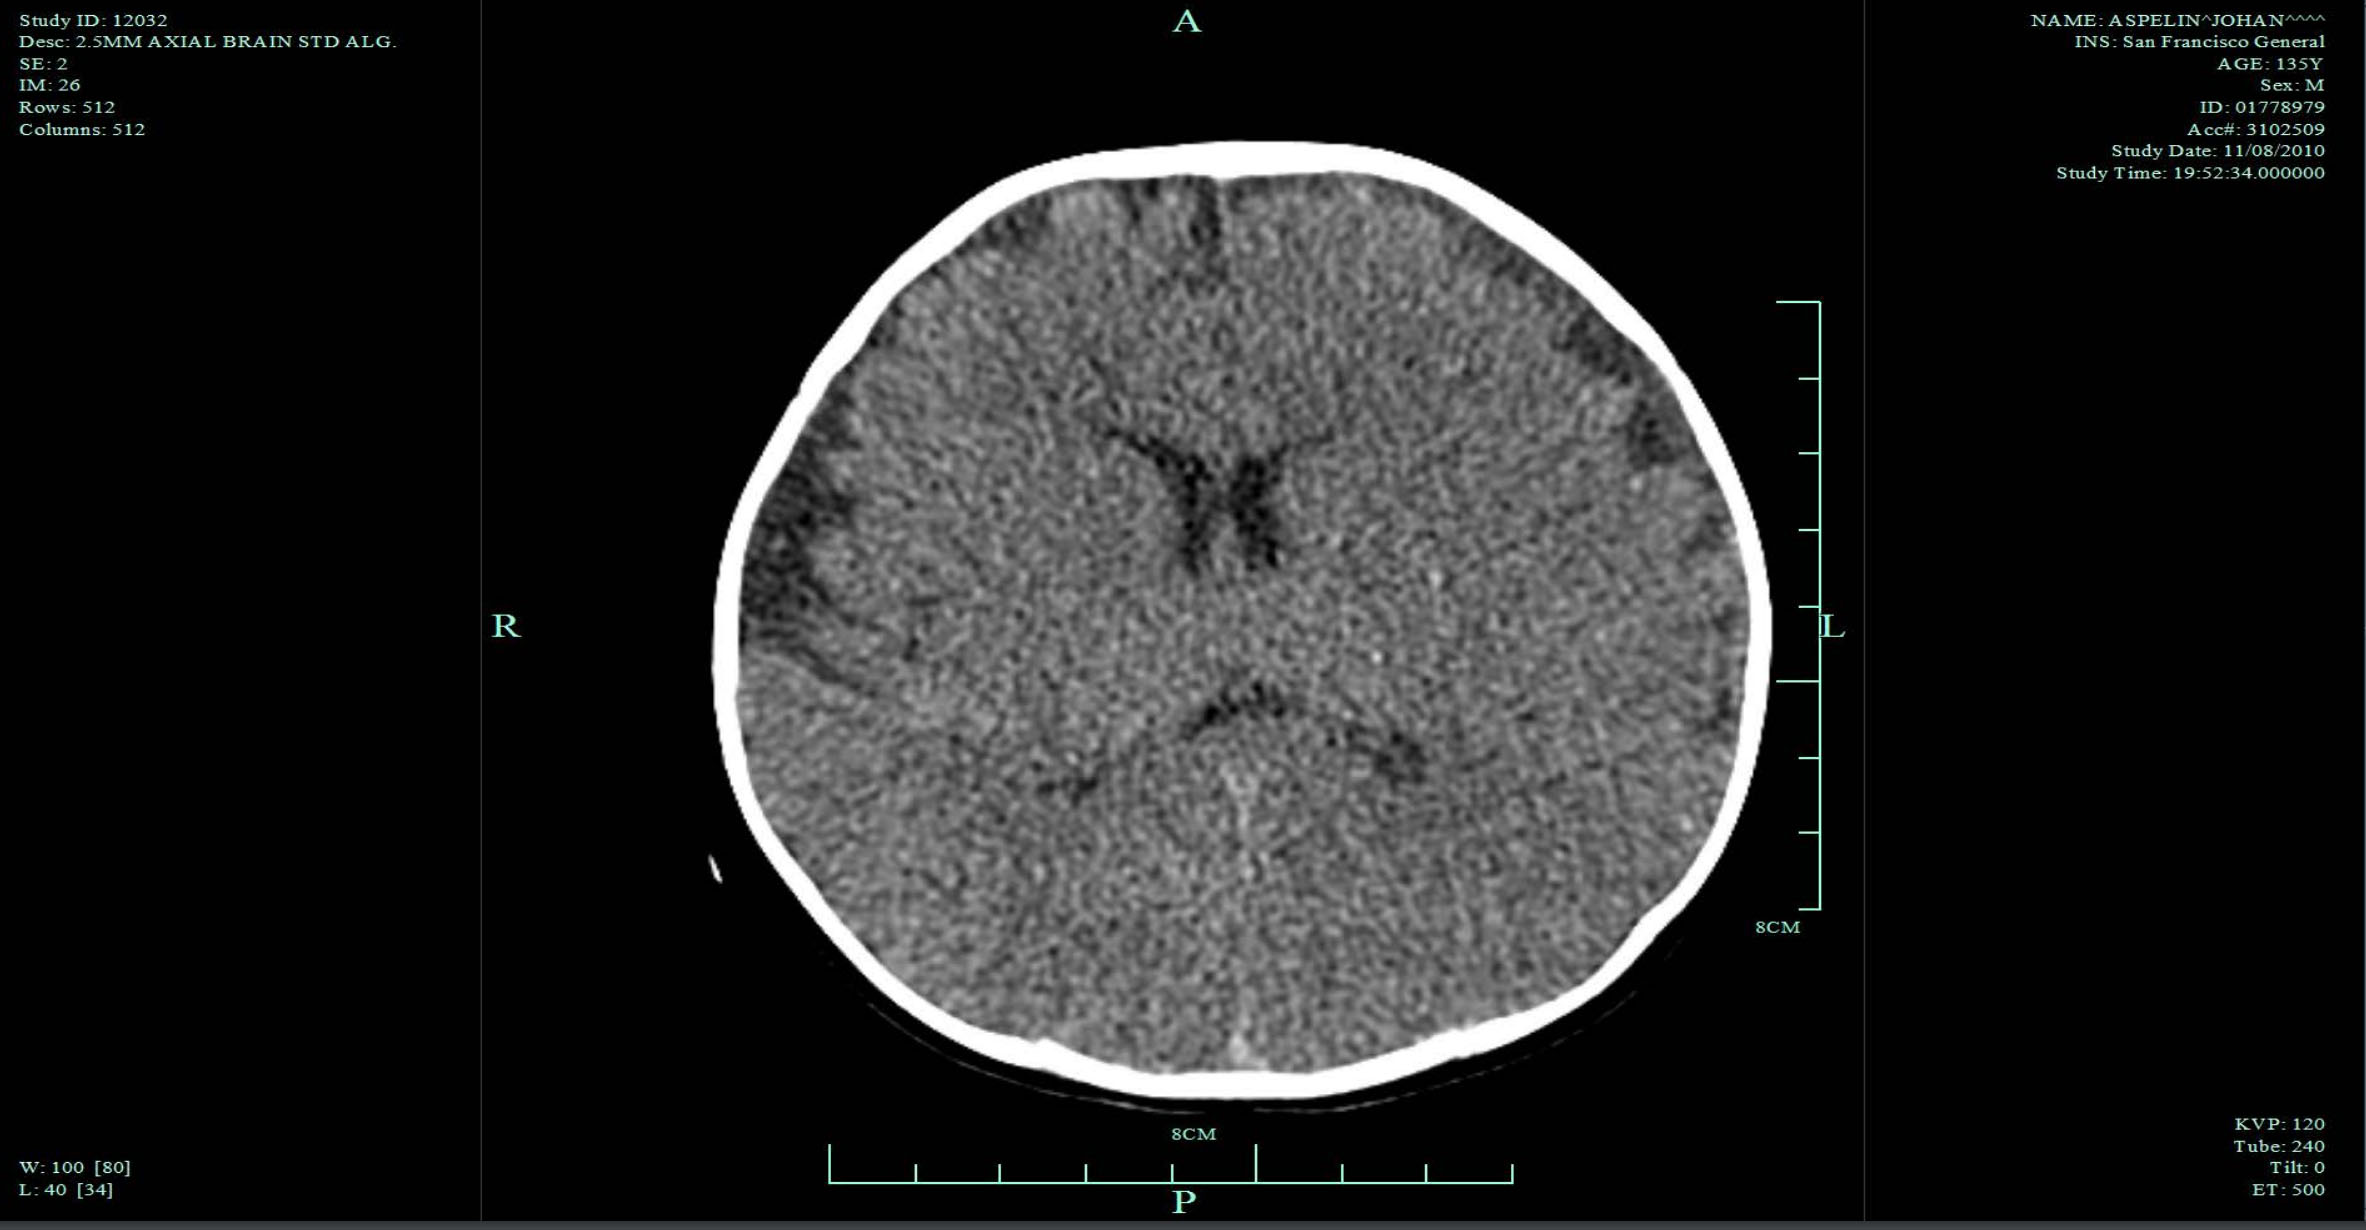

Le père n'était pas tellement nerveux à l'arrivée. Les médecins urgentistes lui ont dit : « Bon, c'est une chute de faible hauteur. Il a un score de Glasgow de 11 ». Cependant, « nous devons réaliser une radio de la tête. » Ils l'ont donc intubé, emmené pour réaliser un scanner et ont alors détecté un très petit hématome sous-dural de deux ou trois millimètres. Ils ont dit aux parents : « Il ira très probablement bien demain matin. » Les médecins ont dit que le pronostic était bon. Puis mon fils m'a téléphoné en Suède et m'a dit ce qu'il s'était passé. J'ai dit, « Bon, un petit hématome, ils ont probablement raison. Il ira bien demain matin, alors ne te fais pas trop de soucis. » Ils ont ensuite effectué un autre scanner six heures après. La plus grande partie du cerveau était alors ischémique. Ils ont réalisé un autre scanner douze heures après. Le scanner a montré un œdème massif. Il allait vers la mort cérébrale.

Mais ce qui est très important, je crois, c'est qu'il nous a fallu trois mois pour recueillir tous les renseignements médicaux concernant les soins prodigués à Johan. Je viens de Suède où tout est numérisé, mais à San Francisco, ça ne l'est pas. On avait des tas de notes manuscrites. Nous avons constaté de nombreux points contestables dans la prise en charge et il nous a alors fallu trois ans pour recueillir des expertises concernant ces soins. Les spécialistes de la maltraitance auraient dû revoir heure par heure ce qui s'était passé dans l'hôpital et chercher des explications s'agissant de l'état de Johan et des valeurs pathologiques de ventilation et d'oxygénation. C'est ce que nous avons dû faire en tant qu'accusé et famille de l'accusé. Nous avons revu chaque détail et chaque résultat d'analyse. Nous avons revérifié chaque scanner. Nous avons parlé avec des experts : « Est-ce une valeur normale ou anormale, quelle peut être l'explication ? » « Quand et comment le fond d'œil a-t-il été fait ? » Nous avons tout passé en revue de cette manière.

Nous avons examiné tous les paramètres relevés lors de l'intubation et nous avons découvert qu'il n'avait pas été correctement intubé — on peut parler d'intubation bâclée. Il n'a pas été correctement intubé pendant six heures. Toutes les valeurs étaient alarmantes, changeantes, hautes et basses. Ainsi, pendant la nuit, il n'y a eu absolument aucun contrôle de la ventilation et de l'oxygénation de Johan. Le poumon gauche tout entier et la partie supérieure du poumon droit s'étaient affaissés, il n’y avait pas de ventilation du tout. Et personne n'avait émis d'observations à ce sujet. Personne. C'est ce que nous avons donc fait afin de relever tous les détails. Et cela prend beaucoup de temps. Pour chaque valeur, absolument chaque valeur qui ne semblait pas correcte, nous avons dû échanger avec des experts pour comprendre. J'ai été très chanceux parce que dans mon hôpital en Suède, je pouvais interroger les meilleurs experts sur ces détails afin de me forger ma propre opinion. Il y avait donc eu une intubation bâclée pendant deux à six heures, des valeurs élevées et basses d’oxygène et de dioxyde de carbone, une mauvaise ventilation, ce qui peut facilement créer une augmentation de la pression intra-crânienne provoquant l'œdème cérébral puis des hémorragies rétiniennes. Il est vraiment absurde de croire qu'en six heures, un enfant en bonne santé peut à partir d'un petit hématome sous-dural, s'acheminer quasiment vers la mort cérébrale et tout cela uniquement à cause d'un secouement alors que le premier scanner est presque normal.

Le spécialiste de maltraitance avait déclaré auparavant que l'histoire rapportée était incompatible avec les constatations, qu'il n'y avait pas de signe de chute. Heureusement, nous disposions d'une expertise en radiologie, alors nous avons commencé à chercher ces signes tel que le gonflement de tissus mous. Quand Johan est entré à l'hôpital, il avait un très petit hématome sous-dural sur le dessus du crâne, et un œdeme d'un à deux millimètres à l'arrière du cerveau, que le radiologiste n'a pas remarqué. Pourquoi en aurait-il fait mention ? Il avait vu les saignements, mais il n'avait pas du tout pensé à de la maltraitance. Le médecin spécialiste de maltraitance n'est pas revenu vers lui et ne lui a pas demandé s'il avait constaté de signes d'une chute de faible hauteur.

Mais nous, nous l'avons fait, et trois jours plus tard, une IRM était réalisée. Et alors, même vous qui n'êtes pas radiologistes pourriez voir qu'il y a un gonflement typique à l'extérieur du crâne et sous la peau, qui est exactement en ligne avec l'histoire du père. Nous avons alors fait d'autres recherches. Nous avons reconstitué des images et nous avons pu voir qu'il y avait très probablement une thrombose veineuse parce qu'elle a été retrouvée à l'autopsie, non pas par le médecin légiste mais par notre expert ; thrombose qui était probablement aussi une conséquence de la chute de faible hauteur et du traumatisme crânien. Nous n’en sommes pas certains, mais c'est très probable.